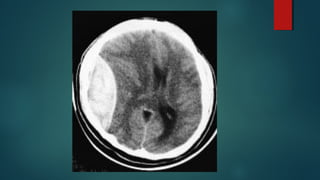

Este documento es el programa para un taller de imágenes del curso de emergencia 2015 impartido por el Dr. Víctor Delgado. El taller se centra en el uso de imágenes médicas para el diagnóstico y tratamiento de pacientes en coma traumático según la base de datos de Marshall. El Dr. Delgado es el único instructor repetido a lo largo del documento.